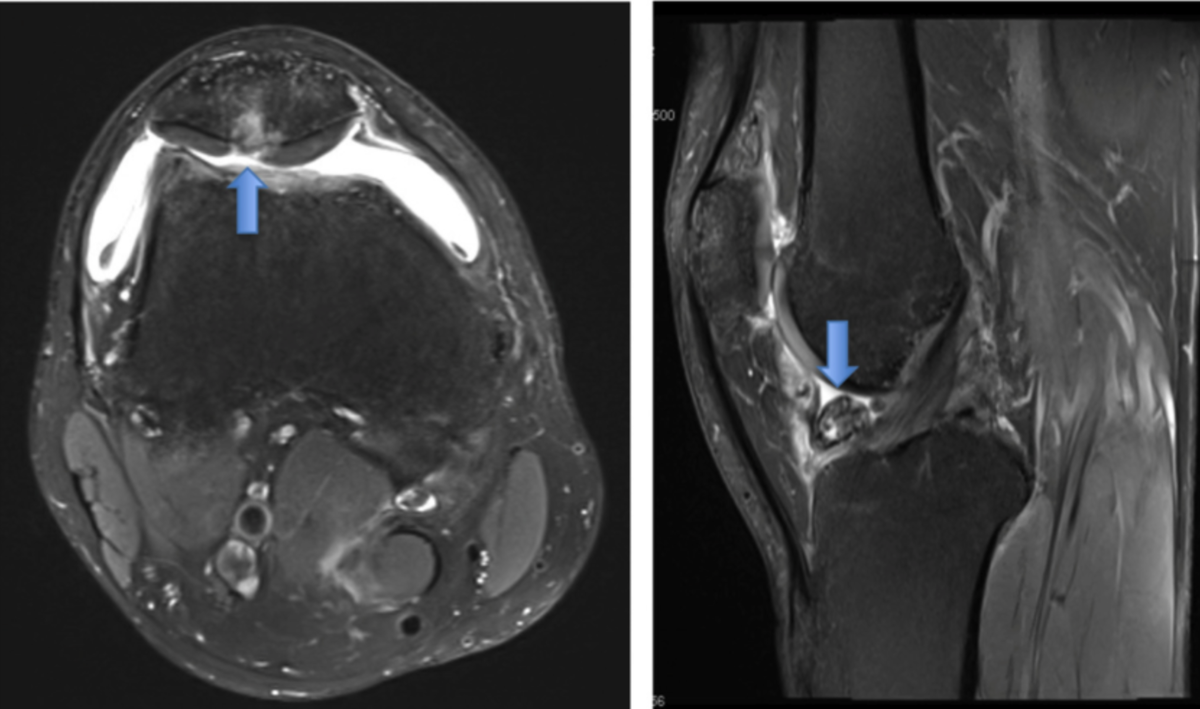

3. Суставы, связки, мениски, хрящи — оцениваются по МРТ!

КТ малоинформативна во всех ситуациях, кроме переломов.